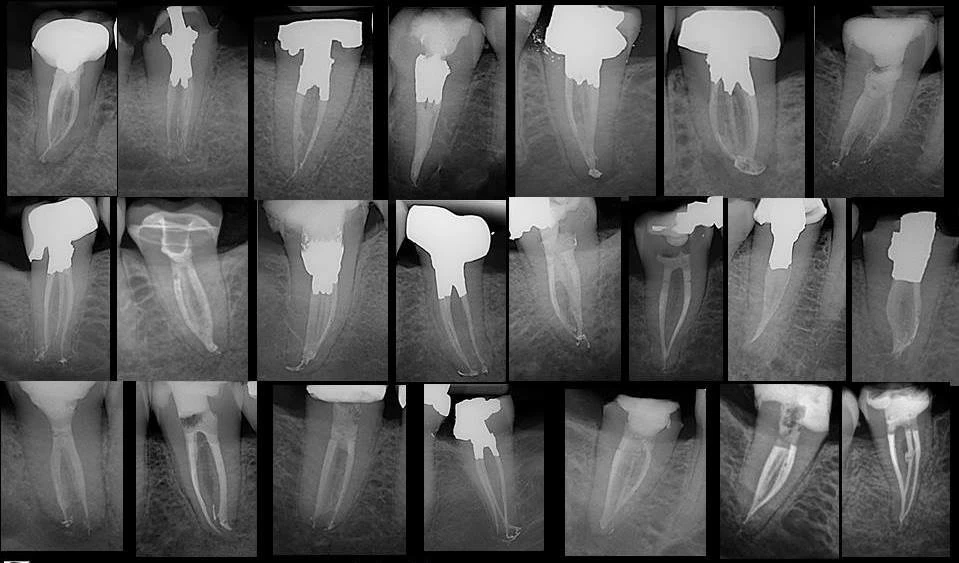

Một phim X-quang đạt tiêu chuẩn tốt có thể ước lượng được cấu trúc mô học này và mặc dù vậy, nếu trên lâm sàng nếu dùng X-quang để xác định điểm thắt chóp từ chóp răng giải phẫu hoặc chóp răng X-quang có thể dẫn đến trám bít ống tủy thiếu hoặc thừa.

Xác định chiều dài làm việc bằng X-quang được sử dụng trong nhiều năm. Chóp răng Xquang được định nghĩa là điểm cuối cùng của chân răng được nhìn thấy trên X-quang, trong khi lỗ chóp là vùng ống tủy giao với bề mặt chân răng, cạnh dây chằng nha chu. Khi lỗ chóp đổ ra mặt bên của chân răng hoặc hướng về mặt ngoài hoặc mặt trong thì nó sẽ khó thấy được trên Xquang.

Olson et al. (1991) nhận thấy rằng khi đưa các trâm nội nha vào ống tủy các răng đã nhổ, chỉ có 82% trâm xuất hiện tại lỗ chóp. Mật độ xương đặc và các câu trúc giải phẫu khác có thể che lấp vùng chóp và không thấy được đầu trâm. Vị trí đặc biệt của xương gò má che lấp hình ảnh X-quang của chóp răng cối lớn thứ nhất hàm trên trong 20% trường hợp và chóp răng cối lớn thứ hai hàm trên trong 42% trường hợp. Sự lắng đọng của ngà răng thứ cấp và xi măng có thể di chuyển điểm thắt chóp lên trên nữa so với giới hạn sai số cho phép khi sửa soạn.

Phim X-quang cung cấp hình ảnh hai chiều của một cấu trúc ba chiều và là kỹ thuật khá nhạy về hình ảnh và độ diễn giải tốt. Cox et al. (1991) nhận thấy rằng khi cần điều chỉnh chiều dài làm việc 68% giám khảo đồng ý rằng cần thiết điều chỉnh lên 0.5mm, trong khi đó chỉ có 14% đồng ý rằng cần thiết điều chỉnh hơn 1.0mm.

Với những lo ngại về nhiễm phóng xạ và tăng cường sử dụng hồ sơ bệnh án lưu trữ điện tử, một số loại máy X quang kỹ thuật số được giới thiệu. Những loại này sử dụng cảm biến (sensor) thay cho phim, và có nhiều ưu điểm hơn các phim X-quang thông thường như giảm tiếp xúc với bức xạ, tốc độ thu nhận hình ảnh và khả năng tăng cường hay chỉnh sửa các hình ảnh. Cederberg et al. (1998) nhận thấy rằng hình ảnh kỹ thuật số lưu trữ huỳnh quang thực hiện cũng như phim Ektaspeed Plus trong việc đánh giá chiều dài làm việc và cho kết quả tốt hơn nhờ các tính năng nâng cao của nó.

Tuy nhiên Friedlander et al. (2002) thấy rằng hình ảnh kỹ thuật số tấm bảng huỳnh quang của trâm nội nha và tổn thương quanh chóp ít rõ ràng hơn so với phim truyền thống, một phần do kích thước điểm ảnh của 64lm lớn hơn so với đầu trâm 06K. Hiện nay, X-quang kỹ thuật số trực tiếp chưa được chứng minh tốt hơn chụp X quang thông thường về chất lượng, thậm chí nó có tăng cường tính năng đo lường, tốc độ cao và liều lượng phóng xạ thấp.

X-quang trước điều trị rất cần thiết trong nội nha để xác định giải phẫu của hệ thống ống tủy, số lượng và độ cong của các chân răng, sự hiện diện hay không của bệnh lý, và đóng vai trò hướng dẫn ban đầu về chiều dài làm việc. Máy định vị chóp điện tử là một công cụ, cùng với Xquang, giúp kiểm soát chiều dài làm việc tốt hơn nhiều.